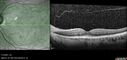

Normal_OCT_line_scan.jpg

Normal OCT line scan296 views00000

71 year old patient with history of laser for melanoma in the right eye. This is the normal 20/20 left eye